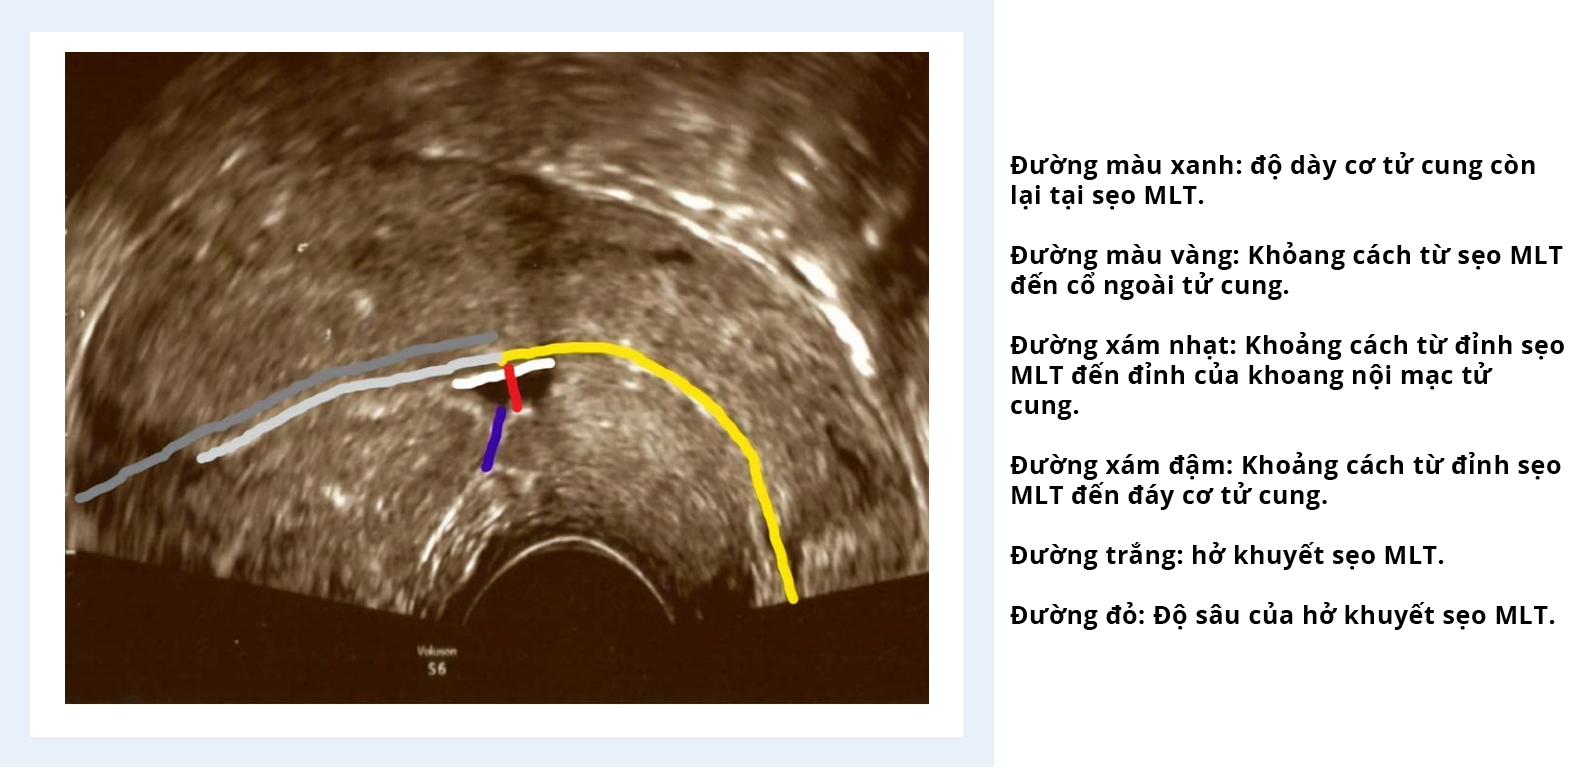

Gần đây, ngày càng có nhiều mối quan tâm về hậu quả lâu dài của việc mổ lấy thai (MLT) đối với sức khỏe và khả năng sinh sản về sau của người phụ nữ. Một trong những di chứng của việc MLT là sự hình thành hở khuyết sẹo MLT trên tử cung, được định nghĩa là hiện diện vùng giảm âm với độ sâu tối thiểu 1 mm ngay tại vị trí sẹo mổ cũ. Sự hiện diện hở khuyết sẹo MLT kèm theo sự hiện diện của dịch trong lòng tử cung đã được mô tả trước đây trong y văn.Sự có mặt của dịch nội mạc tử cung được các chuyên gia y học sinh sản công nhận gây bất lợi lên quá trình làm tổ của phôi. Cụ thể, tỷ lệ mang thai được ghi nhận là giảm đáng kể khi có tích tụ dịch lòng tử cung trong quá trình thụ tinh trong ống nghiệm, và không thể thụ thai được nếu dịch lòng tích tụ nhiều hơn 3,5 mm (He và cs, 2010). Ứ dịch lòng tử cung đã được ghi nhận ở những bệnh nhân bị ứ dịch ống dẫn trứng, hay ít gặp hơn ở những bệnh nhân bị hội chứng buồng trứng đa nang trải qua kích thích buồng trứng để làm thụ tinh ống nghiệm, và thậm chí ở một số bệnh nhân chưa xác định được nguyên nhân.

Một nghiên cứu quan sát tiến cứu đánh giá tình trạng hở khuyết sẹo MLT khi kích thích buồng trứng đã được thực hiện tại Đơn vị hỗ trợ sinh sản IVI Trung Đông, ở Abu Dhabi, Các tiểu vương quốc Ả rập thống nhất từ tháng 6 năm 2018 đến tháng 3 năm 2019 và phân tích hồi quy trên các kết cục thai đến tháng 7 năm 2019. Nghiên cứu thực hiện trên 103 bệnh nhân vô sinh thứ phát (được xác định là không có thai tối thiểu 1 năm sau khi mang thai thành công trước đó) được kích thích buồng trứng để làm thụ tinh ống nghiệm, có tiền căn một hay nhiều lần MLT và có hở khuyết sẹo MLT trên siêu âm. Bệnh nhân được theo dõi thường quy qua siêu âm ngả âm đạo trong quá trình kích thích buồng trứng để điều trị thụ tinh ống nghiệm. Các bệnh nhân trong nghiên cứu được yêu cầu hoàn thành bảng câu hỏi về tiền sử sản khoa. Sự hình thành dịch lòng tử cung cũng như các thay đổi trong đo lường hở khuyết sẹo MLT được ghi nhận lại trong quá trình kích thích buồng trứng bằng siêu âm. Kết quả thai của chu kỳ chuyển phôi trữ ở bệnh nhân có hở khuyết sẹo MLT đã được so sánh hồi cứu với nhóm những bệnh nhân hiếm muộn - không có hở khuyết sẹo MLT trong cùng khoảng thời gian.

Kết quả cho thấy bệnh nhân có hở khuyết sẹo MLT có nguy cơ ~ 40% phát triển dịch ghi nhận được trên siêu âm trong khoang nội mạc tử cung trong quá trình kích thích buồng trứng. Hơn nữa, so với nhóm không có dịch lòng tử cung, nhóm bệnh nhân có phát triển dịch liên quan có ý nghĩa thống kê với độ sâu (cm) của hở khuyết sẹo MLT vào ngày KTBT thứ 2 hoặc thứ 3 (0,57 ± 0,19 so với 0,49 ± 0,18, p = 0,038) và vào ngày trigger (−1 / −2 ngày) (0,64 ± 0,19 so với 0,56 ± 0,19, p = 0,049); chu vi (cm) của hở khuyết sẹo MLT vào ngày trigger (−1 / −2 ngày) (1,79 ± 0,51 so với 1,60 ± 0,5, p = 0,040), khoảng cách từ sẹo MLT đến lỗ ngoài cổ tử cung (cm) (3,25 ± 0,62 so với 2,95 ± 0,73, p = 0,036), số trẻ được sinh ra (3,1 ± 1,8 so với 2,5 ± 1,5, p = 0,047) và số lần MLT trước đó (1,9 ± 1,1 so với 1,4 ± 0,8, p = 0,035). Có sự gia tăng có ý nghĩa thống kê trong các thông số kích thước của hở khuyết sẹo MLT khi kích thích buồng trứng. Nếu tình trạng ứ dịch lòng tử cung được loại bỏ trước khi tiến hành chuyển phôi, kết quả thai sau chuyển phôi (gồm cả tỷ lệ thai và tỷ lệ thai sinh hóa và thai ngoài tử cung, sẩy thai và thai diễn tiến/sinh sống) không khác biệt giữa hai nhóm có và không có hở khuyết sẹo MLT.